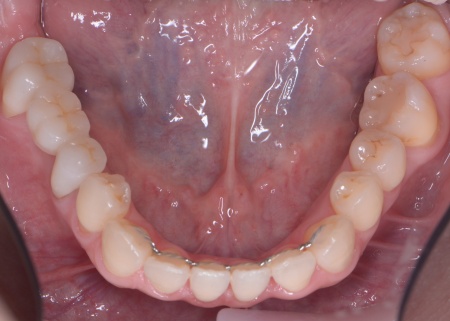

40代女性 矯正治療で噛み合わせを整えたあとセラミックの被せ物・詰め物で修復した症例

まずは矯正治療を優先し、噛み合わせが整ってから虫歯の再発リスクの低いセラミックの被せ物・詰め物などで歯の形態と機能を回復する方針を提案し、同意いただきました。

矯正治療終了後、改めてお口の中を確認したうえで、歯の状態に合わせ虫歯の除去や土台の修復を丁寧に行い、精密な型取りを実施しています。

最後に噛み合わせ全体のバランスを確認しながら新しく作製した被せ物や詰め物を装着し、見た目に問題がないか、噛み合わせが安定しているかを確認し、治療を終了しました。